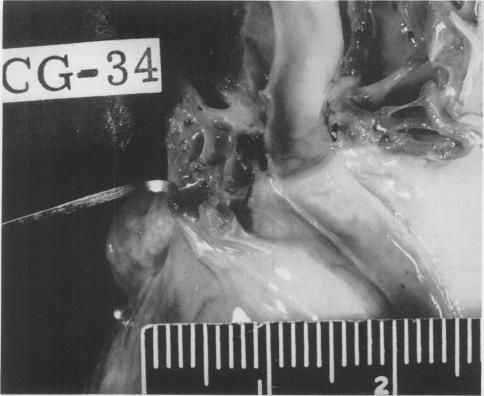

Direct non-suture coronary artery anastomosis in the dog.

Ann Surg. 1958 Aug;148(2):212-8. doi: 10.1097/00000658-195808000-00009.